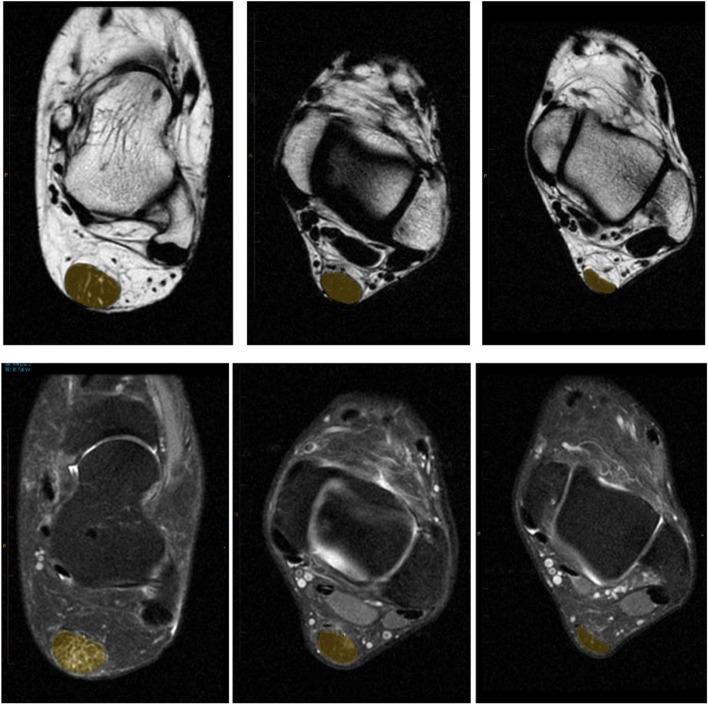

Bilateral MRI scans of Achilles tendons from 30 participants (n = 10 Achilles tendon xanthoma, n = 10 Achilles overuse tendinopathy, n = 10 healthy controls) were analyzed for total lipid content using the Dixon method of fat and water signal separation. Secondary outcome measures included tendon water content, as well as ultrasound characterization of tendon tissue organization and thickness.

Fat content was greater in Achilles tendon xanthomas compared to the tendinopathy (p < 0.0001) and control groups (p < 0.0001). Water content was also greater in Achilles tendon xanthomas compared to the tendinopathy (p < 0.0001) and control groups (p = 0.0002). Ultrasound tissue characterization revealed worse tissue organization in Achilles tendon xanthoma tendons compared to Achilles tendinopathy (p < 0.05) but demonstrated largely overlapping distributions. Achilles tendon xanthoma tendons were, on average, significantly thicker than the tendons of the other two groups (p < 0.01 and p < 0.001, respectively).

对 30 名参与者(n=10 例跟腱黄色瘤,n=10 例跟腱过度使用性肌腱病,n=10 例健康对照组)的双侧跟腱 MRI 扫描进行分析,采用脂肪和水信号分离的 Dixon 法测量总脂质含量。次要结局指标包括肌腱含水量,以及肌腱组织学和厚度的超声特征。

跟腱黄色瘤的脂肪含量明显高于肌腱病(p<0.0001)和对照组(p<0.0001)。跟腱黄色瘤的含水量也明显高于肌腱病(p<0.0001)和对照组(p=0.0002)。超声组织特征显示,跟腱黄色瘤的组织学比跟腱过度使用性肌腱病更差(p<0.05),但分布基本重叠。跟腱黄色瘤的肌腱厚度明显大于其他两组(p<0.01 和 p<0.001)。